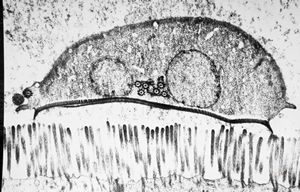

Giardia (Lamblia) intestinalis